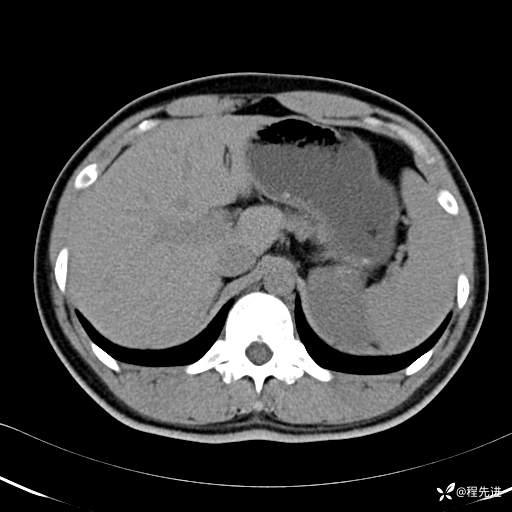

【腹盆】特别精彩病例|体检发现的左侧腹膜后占位期待您的精彩解读

患者年龄:25岁

简要病史:体检发现

CT平扫:(CT值:平扫,27HU,动脉期,27HU,门静脉期,31HU,平衡期,32HU)

CT增强:

动脉期: